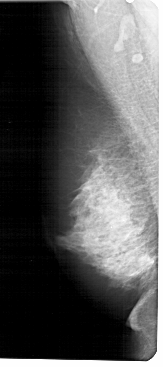

A_1222_1.LEFT_MLO

LEFT_MLO LINES 5491 PIXELS_PER_LINE 2431 BITS_PER_PIXEL 12 RESOLUTION 43.5 NON_OVERLAY